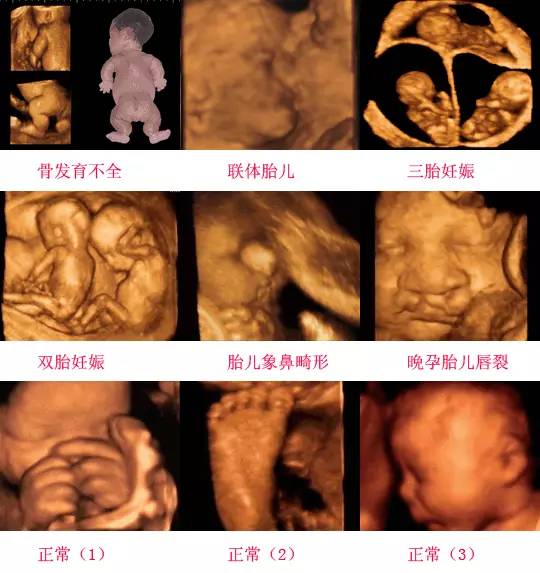

四維彩超是一種先進的醫學影像技術,通過實時觀察胎兒在母體內的活動情況,為醫生提供了豐富的診斷信息,在四維彩超下,我們可以清晰地觀察到胎兒的蛋蛋(睪丸)的形態、位置和大小等特征,胎兒蛋蛋是男性生殖系統的重要組成部分,對于胎兒的生長發育具有重要意義。

四維彩超下胎兒蛋蛋的樣子

在四維彩超下,胎兒蛋蛋呈現出特定的形態和外觀,通常情況下,胎兒蛋蛋呈現出圓形或橢圓形,表面光滑,內部回聲均勻,隨著胎兒的發育,蛋蛋會逐漸增大,并呈現出明顯的性別特征,醫生可以通過四維彩超技術,對胎兒蛋蛋的大小、形態和位置進行評估,以判斷胎兒生殖系統的健康狀況。

四維彩超技術在評估胎兒蛋蛋發育方面具有重要意義,通過四維彩超,醫生可以實時觀察胎兒蛋蛋的形態、位置和大小等特征,了解胎兒生殖系統的發育情況,四維彩超還可以幫助醫生發現可能的異常情況,如睪丸未降、睪丸囊腫等,為及時采取治療措施提供依據。